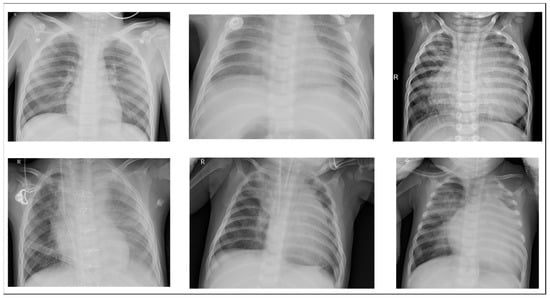

We used an open-source dataset provided by the Kaggle data science competition platform for training (https://www.kaggle.com/paultimothymooney/chest-xray-pneumonia accessed on 25 March 2018) [31]. The dataset comprised thoracic cavity images from child patients (1 to 5 years old) from the Guangzhou Women and Children’s Medical Center, China. These images were classified by two expert physicians and separated into training, test and validation sets. Figure 8 displays the dataset structure, with training sets including 1341 and 3875, test sets 234 and 390, validation set 8, and eight normal and pneumonia images, respectively. Figure 9 and Figure 10 show examples of normal and pneumonia thoracic cavity X-ray images, respectively.

Figure 10. Example pneumonia thoracic cavity X-ray images from the study dataset [31].